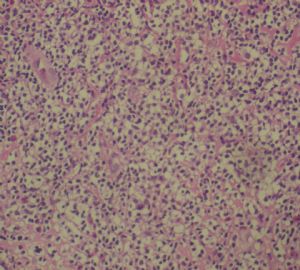

标本名称:  左前臂数个大小不等的皮下肿物。

既往有非何杰金淋巴瘤(滤泡性淋巴瘤)病史22个月。

• 左前臂数个大小不等的皮下肿物     淋巴瘤?图4

图4

病例不错。细胞胞浆透亮,间质血管丰富,图片不是很清晰,似乎有嗜酸粒细胞?

恶性,首先考虑T-NHL。IHC证实。

既往有NHL病史,图片不太清晰,细胞弥漫,胞浆透亮,首先考虑T细胞淋巴瘤。